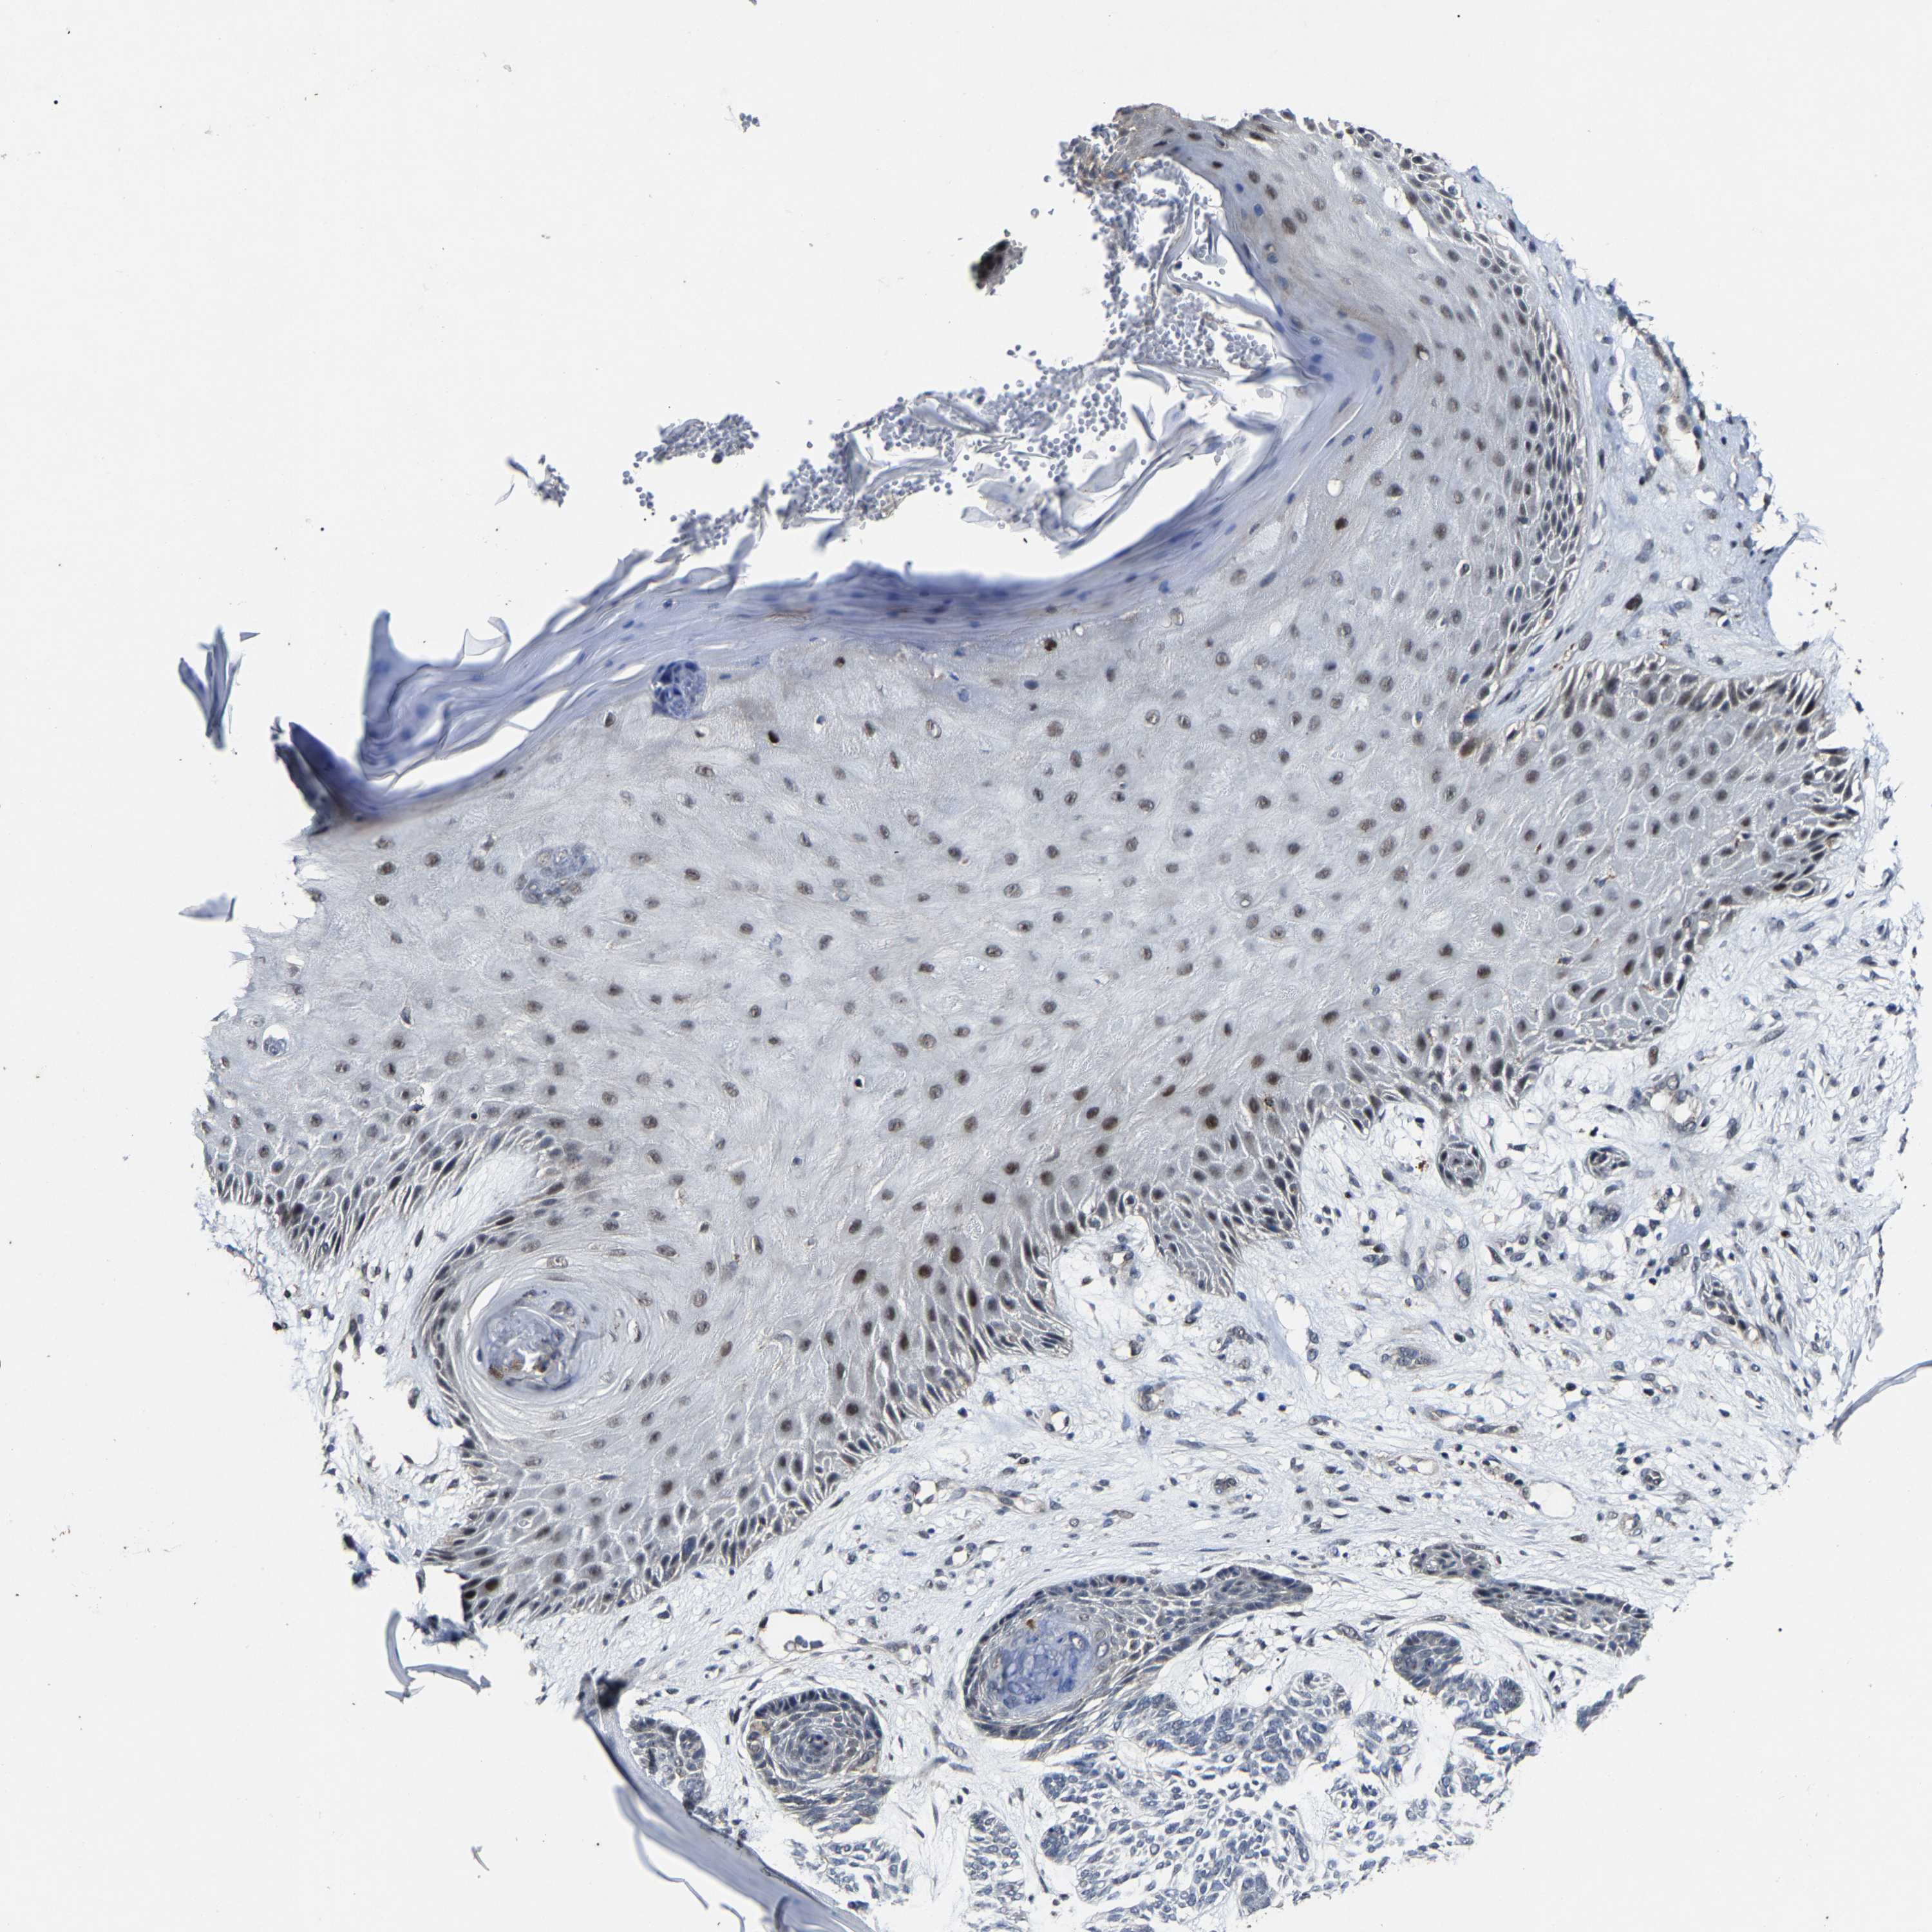

SKIN CANCER - Protein expressioni

A mouse-over function shows sample information and annotation data. Click on an image to view it in a full screen mode. Samples can be filtered based on level of antibody staining by selecting one or several of the following categories: high, medium, low and not detected. The assay and annotation is described here.

Antibody stainingi

Antibody staining in the annotated cell types in the current human tissue is reported as not detected, low, medium, or high, based on conventional immunohistochemistry profiling in selected tissues. This score is based on the combination of the staining intensity and fraction of stained cells.

Each image is clickable and will lead to virtual microscopy that enables deeper exploration of all samples and also displays staining intensity scores, fraction scores and subcellular localization as well as patient and tissue information for each sample.

Antibody HPA020116

Staining

Medium

Intensity

Moderate

Quantity

75%-25%

Location

Nuclear

Squamous cell carcinoma, NOS